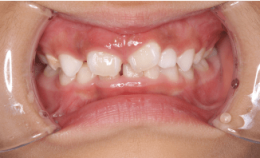

1.上顎前突(出っ歯)

2.下顎前突(受け口)

下顎前突(受け口)とは、奥歯をかみ合わせた際に上下の前歯の位置関係が逆になっており、下の前歯が上の前歯よりも前方に位置している状態のことを指します。